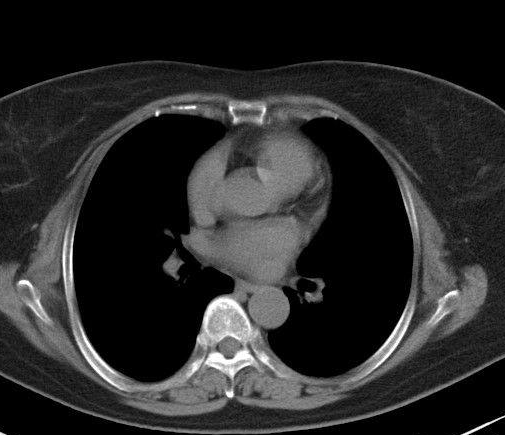

左肺上叶小结节是影像学中的一个描述性术语。左肺上叶小结节,可能是结核所致。肺结核易出现在双肺上部。治疗后可形成瘢痕肉芽组织结构。做透视时,肺部会出现小结节。如果肺癌处于早期,也可以表现为小结节,但大多数出现在中肺和下肺。如无咳嗽、咯血等症状,1-3个月后注意复查结节是否扩大,排除肺部肿瘤。

左肺上叶小结节的病因通常是炎症、结核病、肿瘤等。